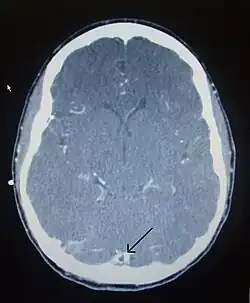

There are various neuroimaging investigations that may detect cerebral sinus thrombosis. Cerebral edema and venous infarction may be apparent on any modality, but for the detection of the thrombus itself, the most commonly used tests are computed tomography (CT) and magnetic resonance imaging (MRI), both using various types of radiocontrast to perform a venogram and visualise the veins around the brain.[3]

Computed tomography, with radiocontrast in the venous phase (CT venography or CTV), has a detection rate that in some regards exceeds that of MRI. The test involves injection into a vein (usually in the arm) of a radioopaque substance, and time is allowed for the bloodstream to carry it to the cerebral veins – at which point the scan is performed. It has a sensitivity of 75–100% (it detects 75–100% of all clots present), and a specificity of 81–100% (it would be incorrectly positive in 0–19%). In the first two weeks, the "empty delta sign" may be observed (in later stages, this sign may disappear).[11] The empty delta sign is characterized by enhancement of the dural wall without intra-sinus enhancement.[6]